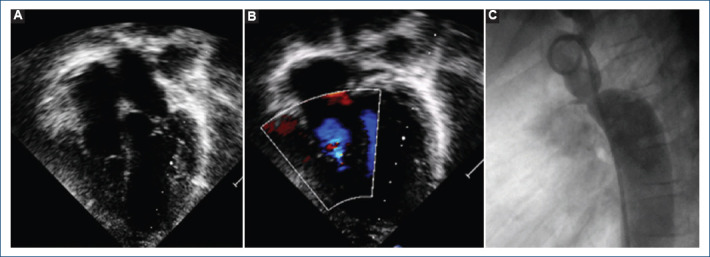

[Percutaneous treatment of aortic coartation and ductus arteriosus in a patient with Ebstein's anomaly].